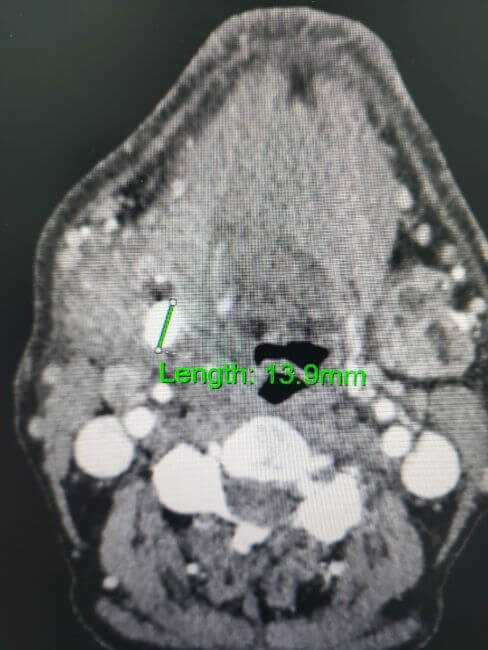

سلام المسيح أمنا ماغي أنا عبدلله داود داود مقيم في لبنان مريض ربو مزمن ومريض قلب وضغط اعاني من فترة من بحصة بالغدة اللعابية مسببة لي ألم مع ورم وصعوبة في البلع بعد الفحص طلب الحكيم اجراء عمل جراحي بأسرع وقت وانا ماعندي إمكانية مادية العملية بتكلف 1400 دولار بطلب منك المساعدة باسم الرب يسوع المسيح